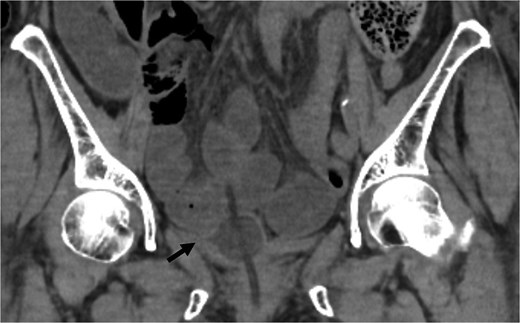

An 82-year-old female with a history of cervical carcinoma presented to our hospital with lower abdominal pain. She had undergone a total hysterectomy decades ago for cervical carcinoma, followed by radiotherapy to the pelvis. Computed tomography (CT) revealed small bowel obstruction attributable to adhesions. The patient was initially diagnosed with adhesion-related small bowel obstruction and was managed conservatively with fasting and intravenous fluid replacement. Although her bowel function promptly recovered within a few days, urinary retention of unknown etiology was noted during hospitalization, necessitating clean intermittent catheterization. When this approach proved insufficient for relieving her symptoms, an indwelling urinary bladder catheter was inserted. Two days after insertion of the catheter, a follow-up abdominal X-ray was performed to confirm recovery of her bowel movement. Imaging revealed indwelling intra-abdominal air above the liver, which was confirmed by emergency computed tomography, raising the suspicion of gastrointestinal perforation (Figs 1 and 2). Clinically, her vital signs were stable, with a heart rate of 65 beats per minute, blood pressure of 113/72 mmHg, and body temperature of 36.6°C, and her abdomen was soft and flat with slight tenderness in the lower abdomen. Laboratory evaluation indicated a C-reactive protein level of 2.31 mg/dl and leukocytes of 5100/mm3. Emergency laparotomy was performed under general anesthesia to rule out potentially life-threatening conditions, such as gastrointestinal perforation. Intra-operatively, perforation of the urinary bladder was identified, with the urinary catheter protruding through the defect (Fig. 3). The bladder wall was extremely thin and fragile, suggesting significant loss of compliance. The bladder rupture was repaired using a two-layer closure with absorbable sutures, and the urinary catheter was repositioned to ensure proper drainage. The patient’s postoperative recovery was uneventful, and she was discharged on postoperative day 25 with the urinary catheter in situ. She was followed up for 70 days, and no signs of intra-abdominal leakage were observed on cystography. The catheter was removed without further complications.

CT indicated intra-abdominal free air (arrows). These findings were later confirmed as being due to bladder rupture.